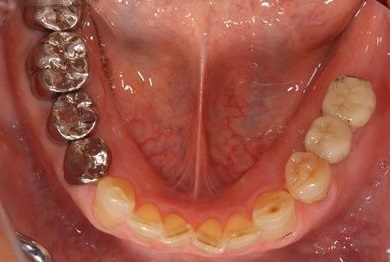

セラミックの症例写真 SHINBI

抜歯即日スピードインプラント治療+歯周外科治療

| 性別/年齢 | 男性 / 62歳 | ||||||||||||||||||||||||||||||||

| 主訴 | 左下の奥歯のブリッジがゆれて、痛みがある。 | ||||||||||||||||||||||||||||||||

| 治療方針 | 抜歯と同時にインプラント埋入を行い、治療期間を短縮する。 | ||||||||||||||||||||||||||||||||

| 治療内容 | インプラント2本(抜歯即日スピードインプラント)、ハイブリッドセラミッククラウン2本、歯周外科治療 | ||||||||||||||||||||||||||||||||

| 総治療費 | 771,960円 | ||||||||||||||||||||||||||||||||

| 治療期間 | 6ヶ月 |